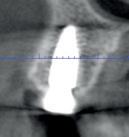

Situation avant la prise d’empreinte en sept. 2009

• Etude de la prothèse sur implants (provisoire, immédiate et définitive).

Situation pré-opératoire 09/2018 09/2018

Contrôle à 10 ans en septembre 2018.